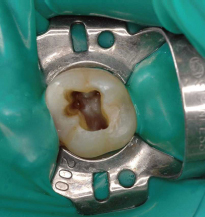

![]() MHアクセスバーNo.1による根管上部形成前 |

![]() MHアクセスバーNo.1による根管上部形成後